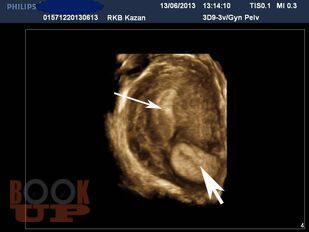

В методических рекомендациях приведен сравнительный анализ существующих методов лечения беременности в рубце на матке после кесарева сечения в нижнем сегменте. Подробно изложен собственный запатентованный протокол лечения рубцовой беременности в зависимости от данных ультразвукового исследования в совокупности с уровнем ХГЧ в сыворотке крови беременной, разработанный авторами. Данный протокол позволяет на основании полученных диагностических данных выбрать оптимальный метод органосохраняющего лечения, определить методы последующего контроля состояния пациента.